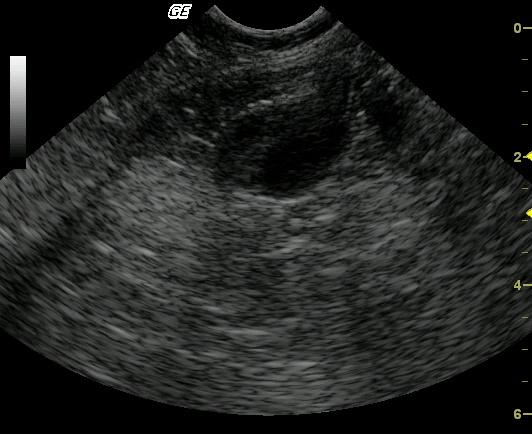

This 2-year-old Maine Coon cat was presented after five days of vomiting and anorexia. The physical examination revealed mildly thickened intestines and 5% dehydration. Blood analysis revealed mild regenerative anemia and slightly elevated globulin levels.